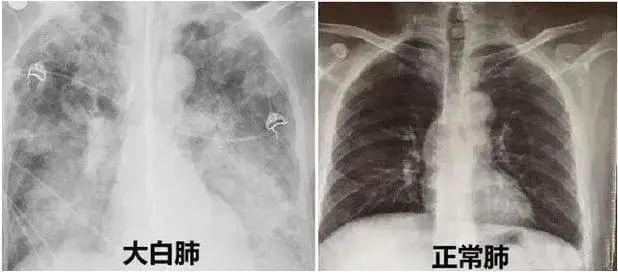

近期,多地醫(yī)生發(fā)現(xiàn)患者出現(xiàn)肺炎或白肺癥狀,引發(fā)關(guān)注。那么什么是白肺呢?其實(shí)白肺是肺部影像學(xué)表現(xiàn)的一個口語化描述。當(dāng)出現(xiàn)炎癥和感染,肺泡被滲出液等填充,在影像學(xué)上的表現(xiàn)就是出現(xiàn)白色區(qū)域。并不是只要肺部出現(xiàn)了炎癥就都叫白肺,一般來講肺部炎癥較重、滲出液較多,白色的影像區(qū)域面積達(dá)到70%?80%時,在臨床上把它稱為白肺。通過“啄醫(yī)生”可以準(zhǔn)確地識別新冠肺炎的典型白肺影像,以下選取幾例最新病例加以說明。

案例一,61歲,女性,確診病例

胸片顯示整個雙肺已經(jīng)白化

影像所見:有慢性阻塞性肺疾病病史。2周前受涼后出現(xiàn)發(fā)熱,伴咳嗽、咳痰。入院后給予吸氧,5天后出現(xiàn)口唇紫紺 ,改為BIPAP呼吸機(jī)輔助通氣。12月14日和12月18日,兩肺病灶自肺野外周、下后部向中心和上部迅速擴(kuò)展,表現(xiàn)為“白肺”。